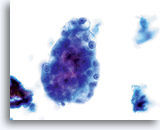

Cytologically, Type I neoplasms show atypical/malignant endometrial cells upon an increased maturation index background. By contrast, Type II neoplasms usually show upon an atrophic background. On ThinPrep samples the endometrial cells will be well preserved and may appear in 3-dimensional crowded groupings of varying sizes as well as small flat sheets containing few cells. The cells usually appear larger than their normal counterpart and the groups have smooth, sometimes scalloped borders giving them a papillary configuration. The cytoplasm is finely to discretely vacuolated and some larger vacuoles can be observed compressing the nucleus to one side of the cell as well as occasionally exhibiting polymorphonuclear cell engulfment. Nuclear features vary dependent upon the grade of the tumor. In general, as the tumor becomes less differentiated, the nucleus tends to round up with an associated gradual increase in nuclear area (µm2), size and number of nucleoli, irregularities in the distribution and coarseness of the chromatin and thickening of the nuclear membranes.

Polymorphonuclear cells may be engulfed in the cytoplasm. 60x

Overall cell size is usually larger than the normal counterpart. 60x

Nuclei “round up” compared to the normal nucleus. 60x

Nuclear membranes may be thickened. 60x

Chromatin may be clumped and irregularly distributed. 60x

Nucleoli are common and vary in frequency, size and number. 60x

Tumor diathesis and single malignant cells may be noted. 60x

Tumor diathesis may be present and appears as a “woven shroud” with a denseness or linear presentation of debris in the center and a frayed or pulled out appearance of the material around the edges of the group. 60x

Endometrial adenocarcinoma 60x